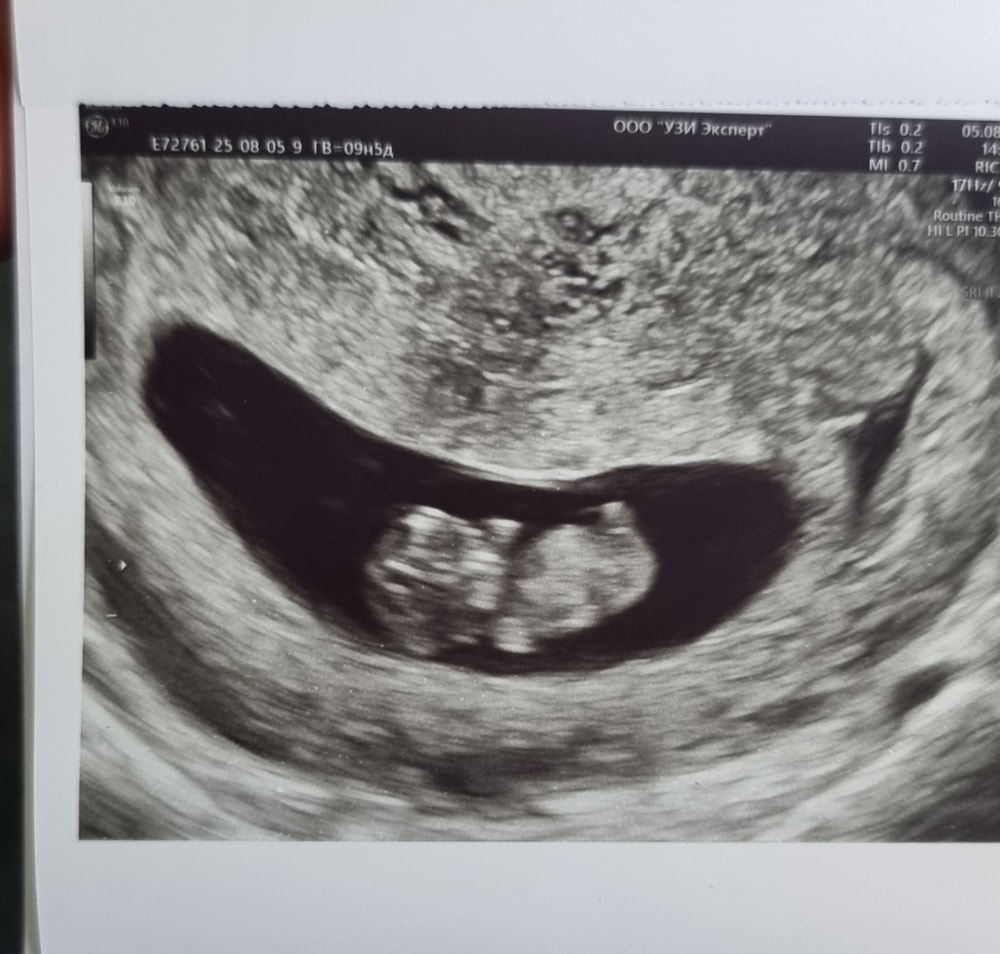

Девочки, всем привет . У меня вторая берем, первая закончилась выкидышем на 8-9 неделе. Очень переживаю за рост хгч , поделитесь пожалуйста своими историями и как вы думаете норма у меня или нет. Сейчас срок 5.3 недели

Сдавала 8.09 - было 1031,

12.09 - 2877

14.09 - 3451 .

с 8 по 12 еще норм, а вот с 12 по 14 число прям совсем мало, очень переживаю 😭